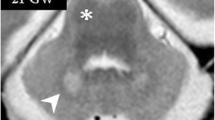

Rostrocaudal sequence of the levels and landmarks analyzed in this study taken from case 9. 1A: MRI image of the LI level. The straight white line shows the fronto-temporal junction, a few millimeters after LI and the beginning of the EC; this point is about 1 mm in front of the start of A (dashed line). 2A: MRI image of A. The solid line shows the outline of the LV. 3A: MRI image of Hh. The dashed line shows hippocampal digitations, while the solid line shows the outline of the LV. Images 1B–3B: histological sections corresponding to the same levels as in the left-hand side column (scale bar: 1 cm). 1C–3C: approximate levels (white section plane) in a ventrolateral image of one complete hemisphere (scale bar: 0.5 cm). Abbreviations: ac, anterior commissure; Cl, claustrum; cs, collateral sulcus; FG, fusiform gyrus; GS, gyrus semilunaris; GU, gyrus uncinatus; hf, hippocampal fissure; Hh, hippocampal head; Ins, insula; ITG, inferior temporal gyrus; MTG, medial temporal gyrus; ot, optic tract; Pu, putamen; STG, superior temporal gyrus; TCl, temporal claustrum

Rostrocaudal sequence of the levels and landmarks analyzed in this study taken from case 9. 1A: MRI image of LGN. The dashed line shows the surface of LGN and MGN in the LV. 2A: MRI image of Pul. The dashed line shows the separation between Pul and H. 3A: MRI image of Fx (dashed line). Images 1B–3B: histological sections corresponding to the same levels (scale bar: 1 cm). 1C–3C: approximate levels (white section plane) analyzed in a ventrolateral image of the whole hemisphere (scale bar: 0.5 cm). Abbreviations: cas, calcarine sulcus; chpx, choroid plexus of the lateral ventricle; cp, cerebral peduncle; H, hippocampus; its, inferior temporal sulcus; MGN, medial geniculate nucleus; mts, middle temporal sulcus; ots, occipito-temporal sulcus; PPH, posterior parahippocampal cortex; RSP, retrosplenial cortex; scc, splenium of the corpus callosum